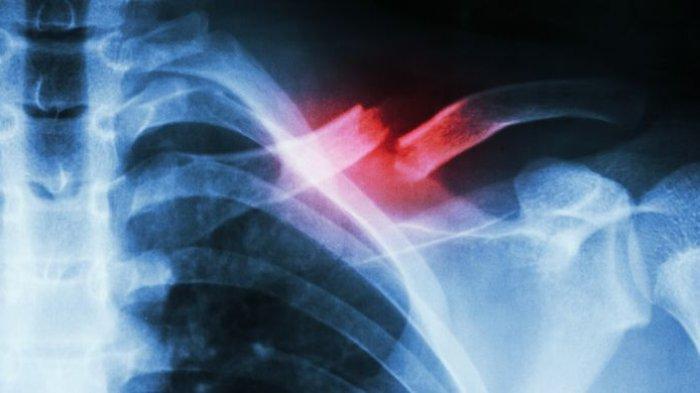

ilustrasi patah tulang clavicula

TRIBUNHEALTH.COM - Clavicula adalah tulang yang berada pada daerah dada dan menghubungkan tulang tangan dengan dada.

ilustrasi patah tulang clavicula (health.kompas.com)